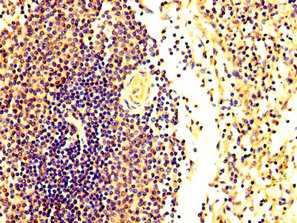

IHC image of CSB-PA882149LA01HU diluted at 1:300 and staining in paraffin-embedded human spleen tissue performed on a Leica BondTM system. After dewaxing and hydration, antigen retrieval was mediated by high pressure in a citrate buffer (pH 6.0). Section was blocked with 10% normal goat serum 30min at RT. Then primary antibody (1% BSA) was incubated at 4°C overnight. The primary is detected by a biotinylated secondary antibody and visualized using an HRP conjugated SP system.